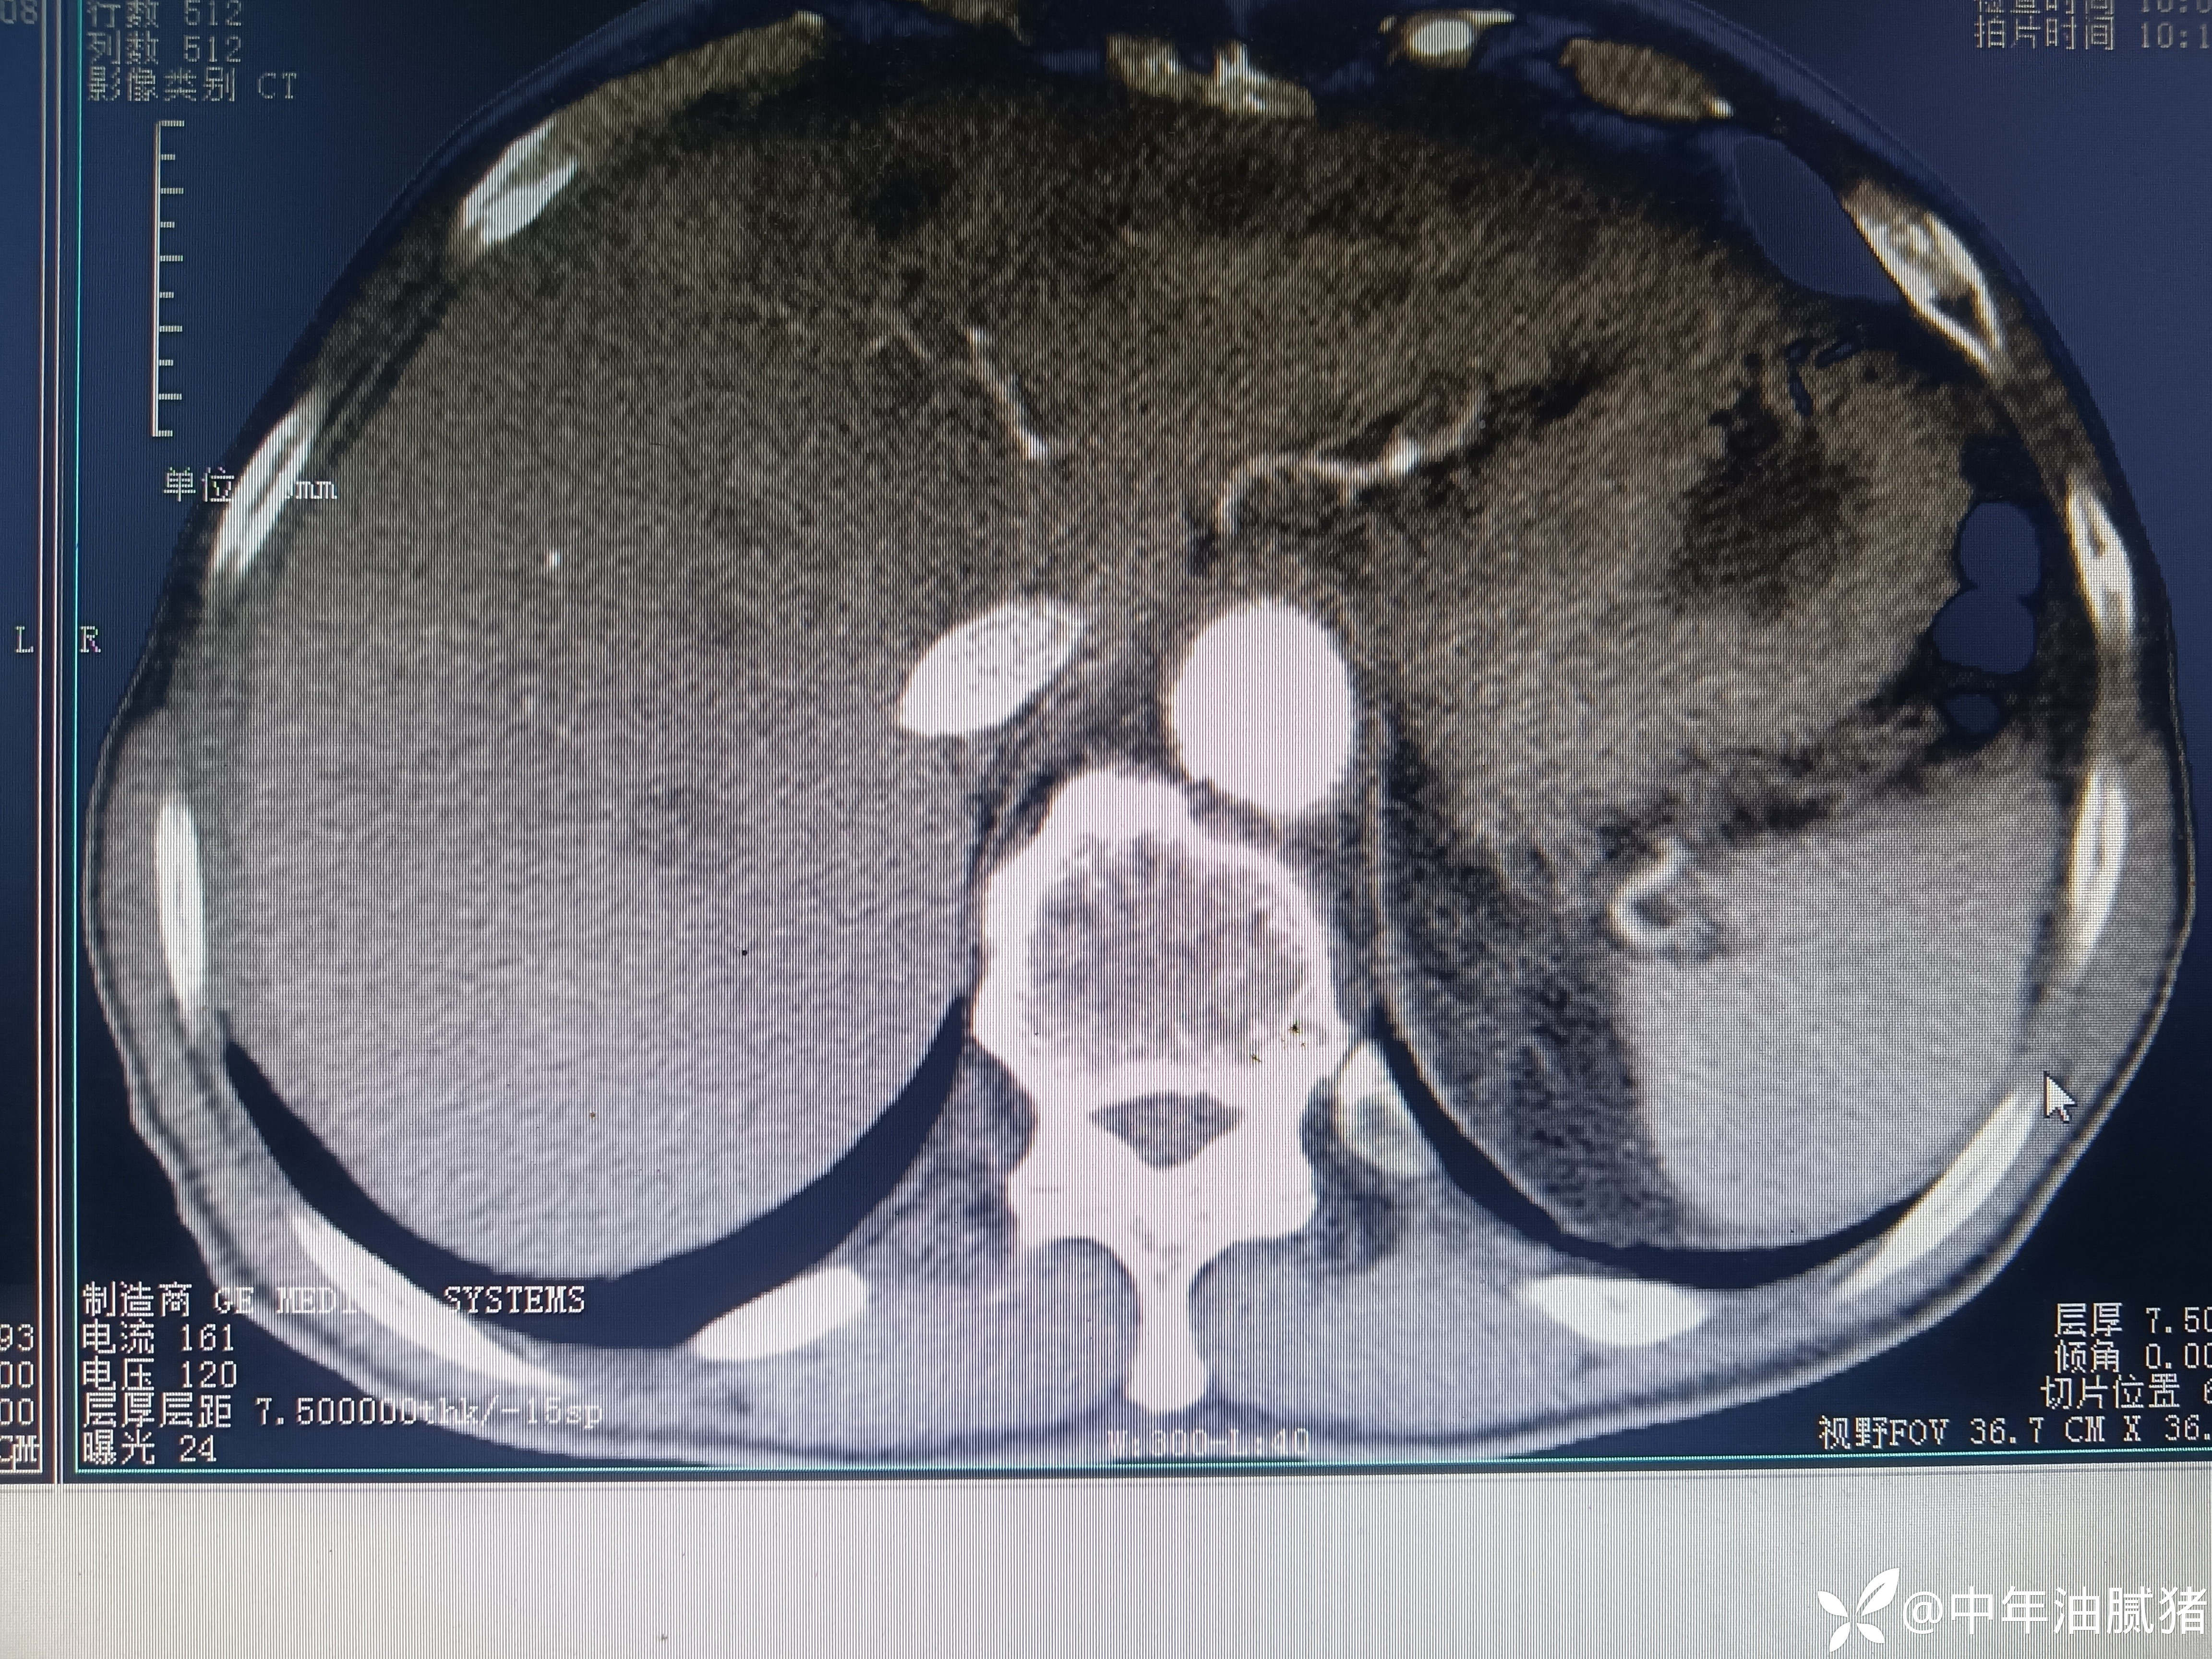

肺ct看到肝内病灶,行增强检查

男,72岁,感胸痛7天,不剧,咳嗽时略明显,有吸烟,行肺ct报告如下

建议增强ct.报告如下

考虑肝囊肿?让他走?

看后,我隐隐约约觉的不是肝囊肿那么简单?元芳,你怎么看?狄阁老,我也是这么认为!摇人,掏起手机:喂,w主任,请帮我看看这个ct。5分钟后报告修改如下